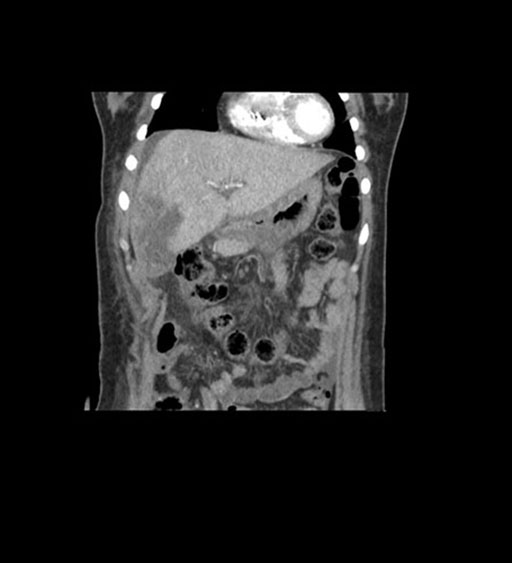

Imaging Analysis

Look through the patient's CT scan to identify any areas of concern for the necessary procedure.

Coronal Arterial

Coronal Venous